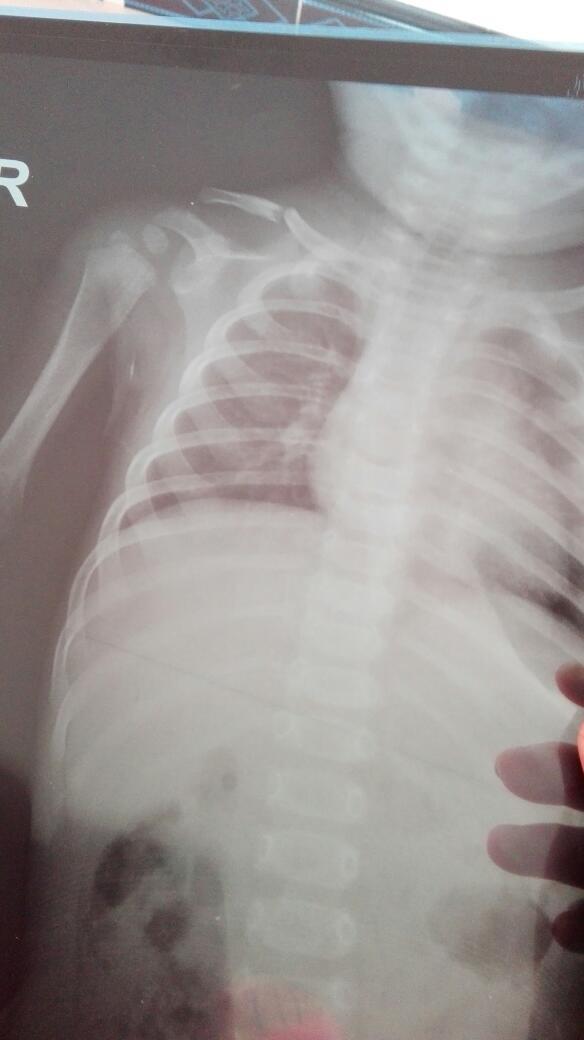

七个半月的宝宝锁骨完全性断裂不固定能长好吗 点击展开 匿名用户 2016-05-03 07:50 满意回答 锁骨骨折最主要的就是固定,不固定需要警惕骨骼长错位 cn#BkQfGLQBkk 2016-05-03 09:09 宝宝知道提示您:回答为网友贡献,仅供参考。 相关问题 新生儿 锁骨皮肤下长了囊性小结节会自己消退吗 七个半月宝宝嗓子感觉很紧似的,喘,生下来一直这样是不是哮喘呀?锁骨有点高!有知道什么原因吗? 六个半月的女宝宝锁骨跟后背到臀部头皮也有都是红点点比痱子大点擦了药也没见好是怎么回事啊?